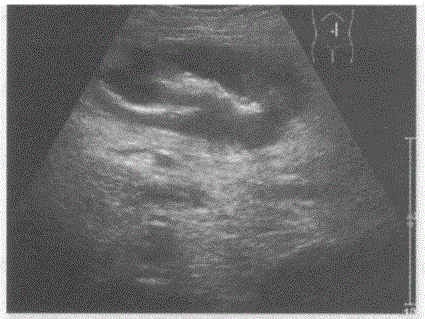

问题 临床资料:男,60岁,自述左中腹可触及一肿物。 化验检查:便潜血阳性。 超声综合描述:右上腹扫查可见假肾样低回声区,中部可见气体样强回声,周边回声低。 超声提示:

选项 A.小肠壁增厚(肠癌) B.慢性结肠炎 C.阑尾周围脓肿 D.小肠正常声像图

答案 A